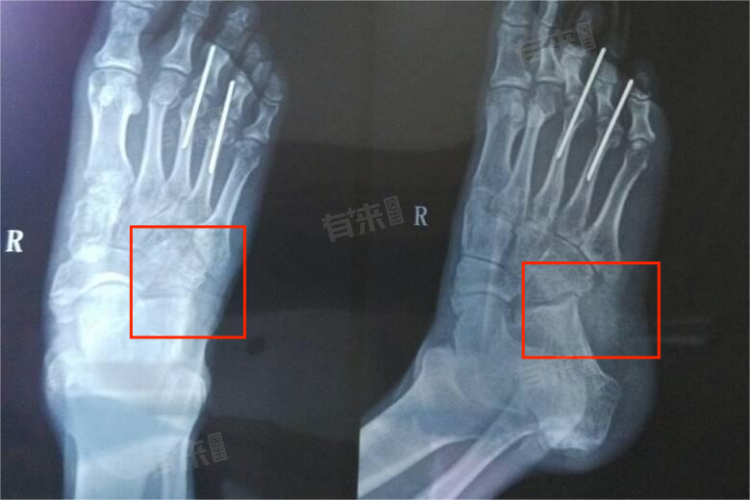

- 对于大多数撕裂性骨折患者而言,尤其是骨折部位复杂、骨折程度较重、或伴有明显移位的患者,其恢复时间往往需要更长。这类患者通常需要接受手术治疗,如切开复位内固定等,以确保骨折片能够准确复位并得到有效固定。术后,患者还需要进行一段时间的康复锻炼,以促进骨折愈合和关节功能恢复。在这种情况下,患者通常需要3个月或更长的时间来完全恢复。